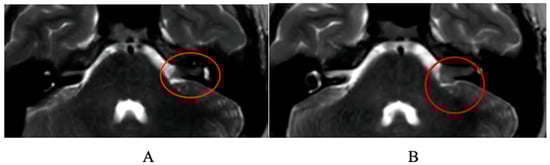

A Case Report of Malignant Cerebellopontine Angle Lesion Highlighting the Interdisciplinary Diagnostic Challenge in the Case of Unilateral Progressive Hearing Loss

1. Case Report